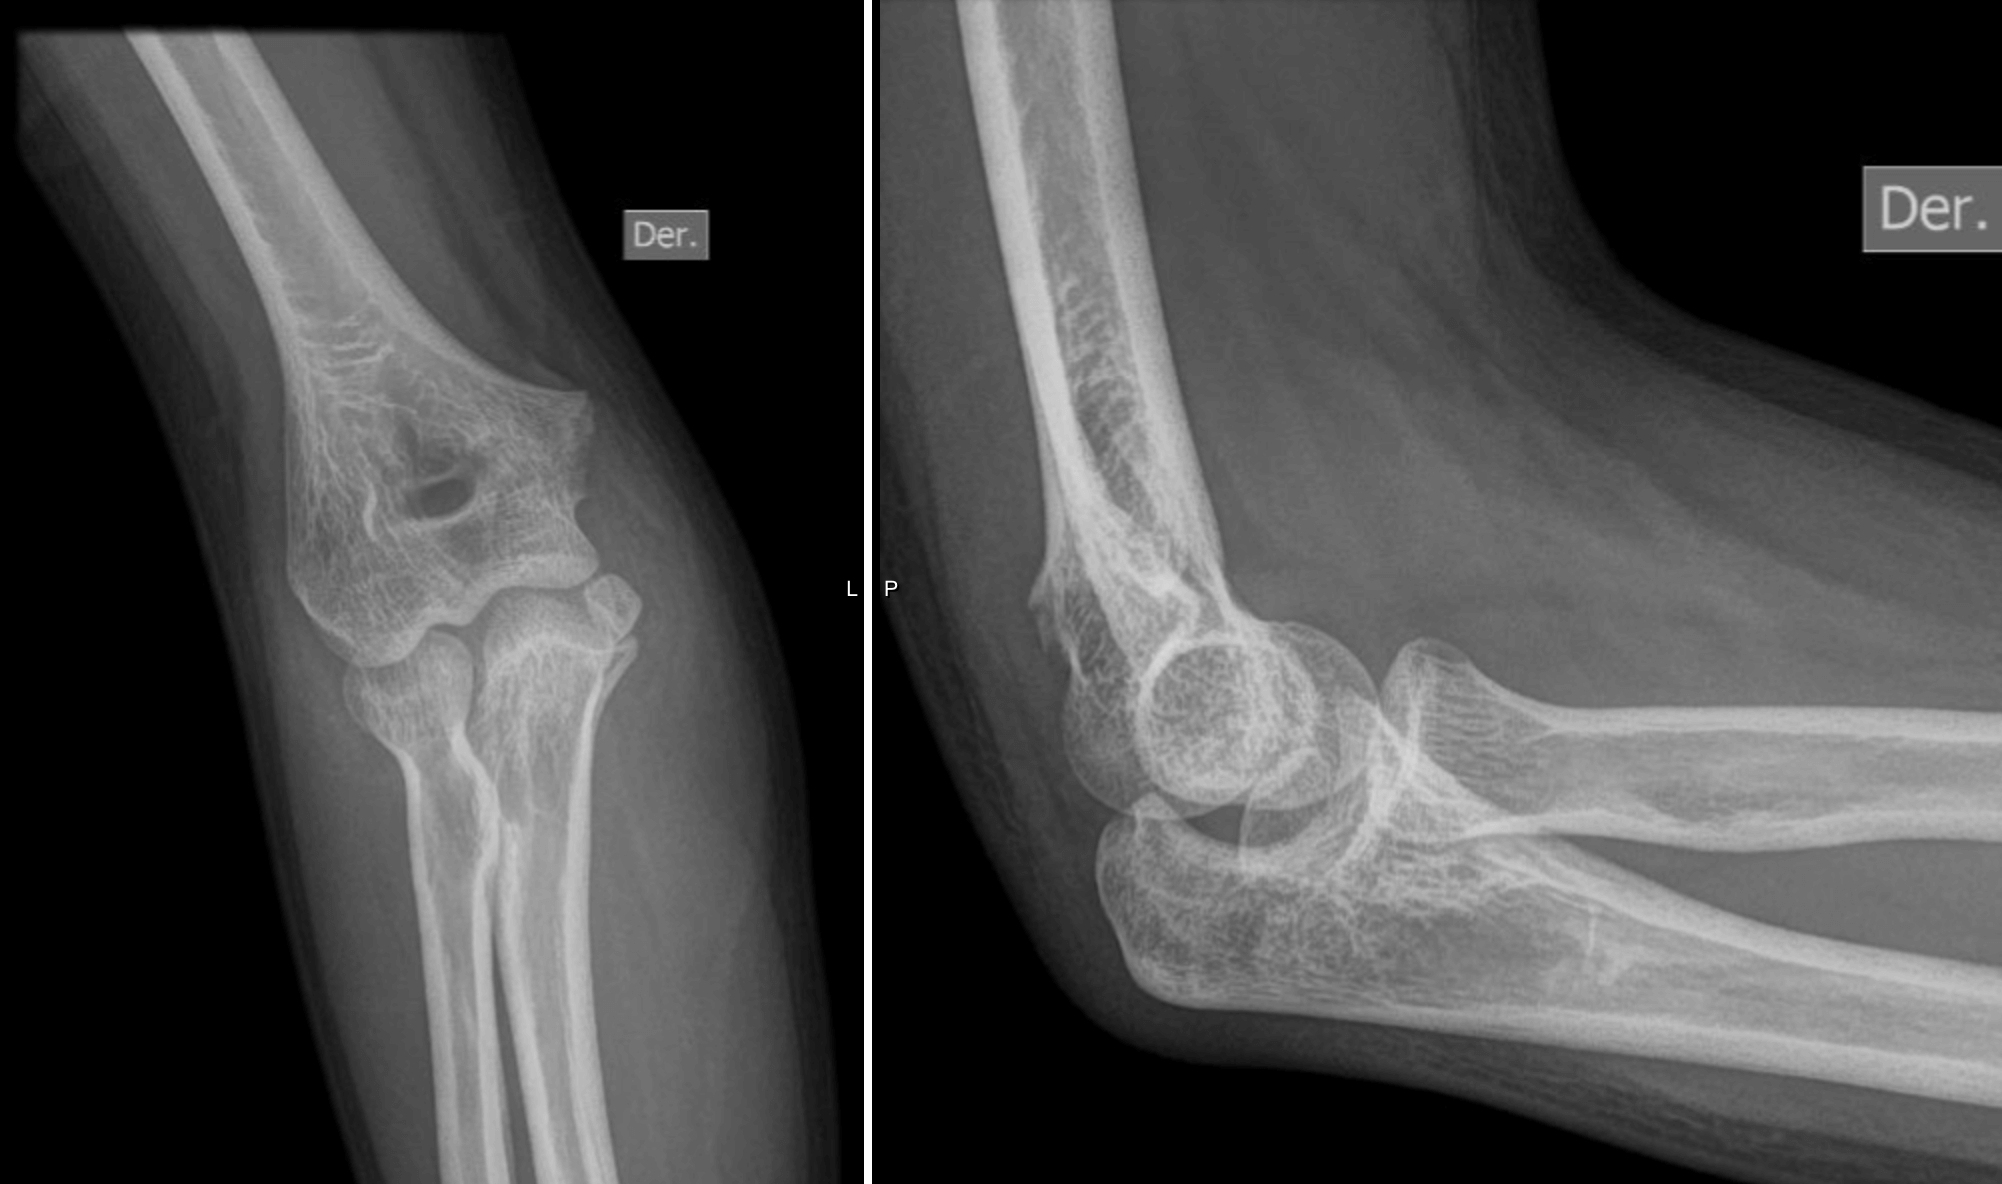

Luxación de codo AP: Ciertos accidentes pueden ocasionarnos que el codo se “safe” esto consiste en la dislocación o luxación del húmero distal del olécranon y de la cúpula radial. En esta radiografía vemos como se observa desde frente la lesión, y en la siguiente →

Luxación de codo LATERAL: observamos cómo se diagnóstica la luxación de codo en una radiografía desde perfil.